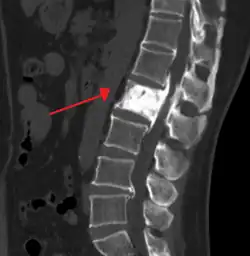

- Pagetic bone has a characteristic appearance on X-rays. A skeletal survey is therefore indicated.

- Bone scans are useful in determining the extent and activity of the condition. If a bone scan suggests Paget's disease, the affected bone(s) should be X-rayed to confirm the diagnosis.